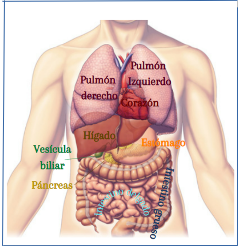

– Visceral. La osteopatía visceral está orientada a favorecer el adecuado funcionamiento de los órganos y de los elementos con lo que se relacionan para garantizar el equilibrio estructural de dicho órgano. En este aspecto los factores que influyen son el sedentarismo y la alimentación.